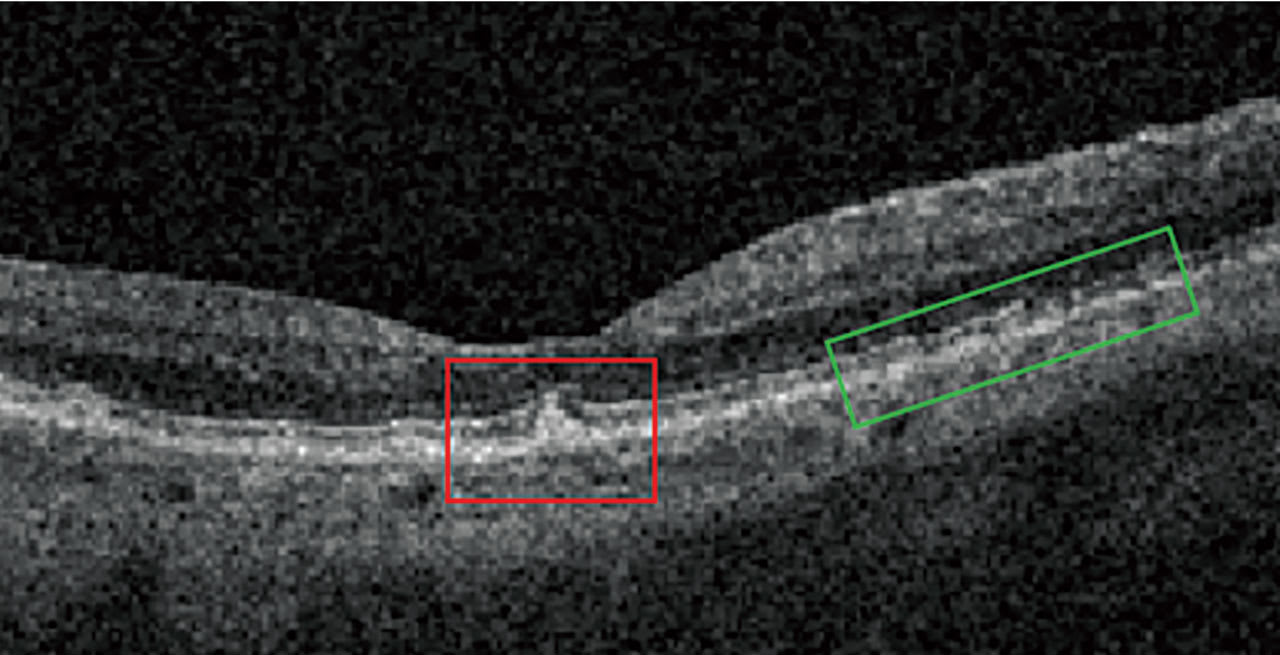

Nascent GA is drusen-associated incomplete RPE and outer retinal atrophy (iRORA) without CNV.1,2 On OCT, it appears as a subsidence of the outer plexiform layer (OPL) and the inner nuclear layer (INL), along with a wedge-shaped band within the OPL.1 The lesion’s boundaries are defined by “an abrupt increase in choroidal reflectivity below Bruch’s membrane; the RPE, photoreceptor, and choriocapillaris layer loss; and external limiting membrane absence/descent”.1 Also, nascent GA and iRORA increase progression risk to GA. In fact, eyes that have some of the findings of iRORA are at high risk of developing advanced AMD3 (Figure 2).

On OCT, drusen appear as RPE elevations. Calcified drusen have a hyporeflective core surrounded by a hyperreflective area on OCT (Figure 3). Patients who have heterogeneous internal reflectivity within drusen (HIRD) have a 6-fold risk of progressing to advanced AMD within a year.4

Reticular Pseudodrusen and Subretinal Drusenoid Deposits Reticular pseudodrusen (RPD), also called subretinal drusenoid deposits (SDD), are anterior to the RPE layer and have a reticular pattern of yellow-white lesions on CFP. RPD are associated with multifocal GA lesion development.1 On OCT (Figure 3), RPD are hyperreflective above the RPE (drusen are below the RPE). Patients who have RPD have a 2-fold increased risk of progressing to advanced AMD.5

IHRF are small, punctate structures that are hyperreflective on OCT. They are mostly located in the INL and OPL. Patients with IHRF are at risk of developing GA within 2 years by 5-fold (see “Comparing Biomarker Progression Risks,” below).6